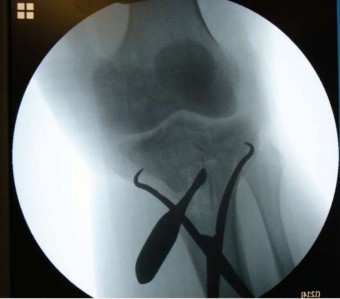

Hình 1.9 Hai loại khung cố định ngoài hybrid được dùng điều trị gãy mâm chày.

Năm 1994, Stamer và cộng sự [113] nghiên cứu 23 gãy mâm chày loại VI theo Schatzker điều trị bằng khung cố định ngoài hybrid (Hình 1.9). Trong đó có 8 trường hợp mở tối thiểu để nắn xương và cố định bên trong trước khi đặt khung; những trường hợp còn lại được cố định bằng bắt vít xốp qua da trước khi đặt khung cố định ngoài. Kết quả có 13 trường hợp rất tốt, 3 tốt, 1 trung bình và 6 kém. Kết quả kém ở những bệnh nhân bị nhiễm trùng hoặc bị nhiều chấn thương khác ở hệ cơ xương làm giảm điểm số khi đánh giá theo thang điểm. Stamer cho rằng đây là phương pháp tạo được sự bất động tốt và cho phép vận động sớm trong những trường hợp gãy mâm chày phức tạp.